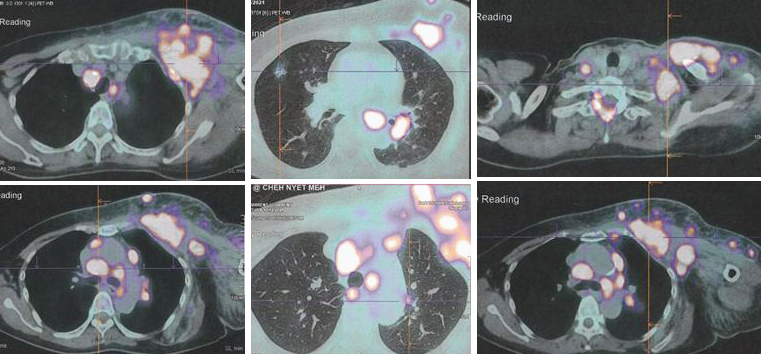

Due to the massive metastasis as shown in the PET scan done on 10 December 2021, Lucy had no choice but to proceed with chemotherapy. Indeed the cancer had spread extensively.

1. Amazing results of chemotherapy. Compare these three pictures –

Left: After surgery Lucy was on alternative therapy, refusing to undergo chemotherapy. The result was extensive metatastasis (middle). Right: Lucy has no choice but to go for chemotherapy. The outcome of 6 cycles of chemotherapy was just fantastic! In my 25 + years dealing with cancer patients, I have never seen such a great outcome of chemotherapy. Salute the oncologist! You rescued her!

In fact, the results were so unbelievable that one is tempted to ask if it is for real and not a fake? My answer is NO, detailed study of the PET scan results below are real! Study the images carefully – those before and after  chemotherapy.